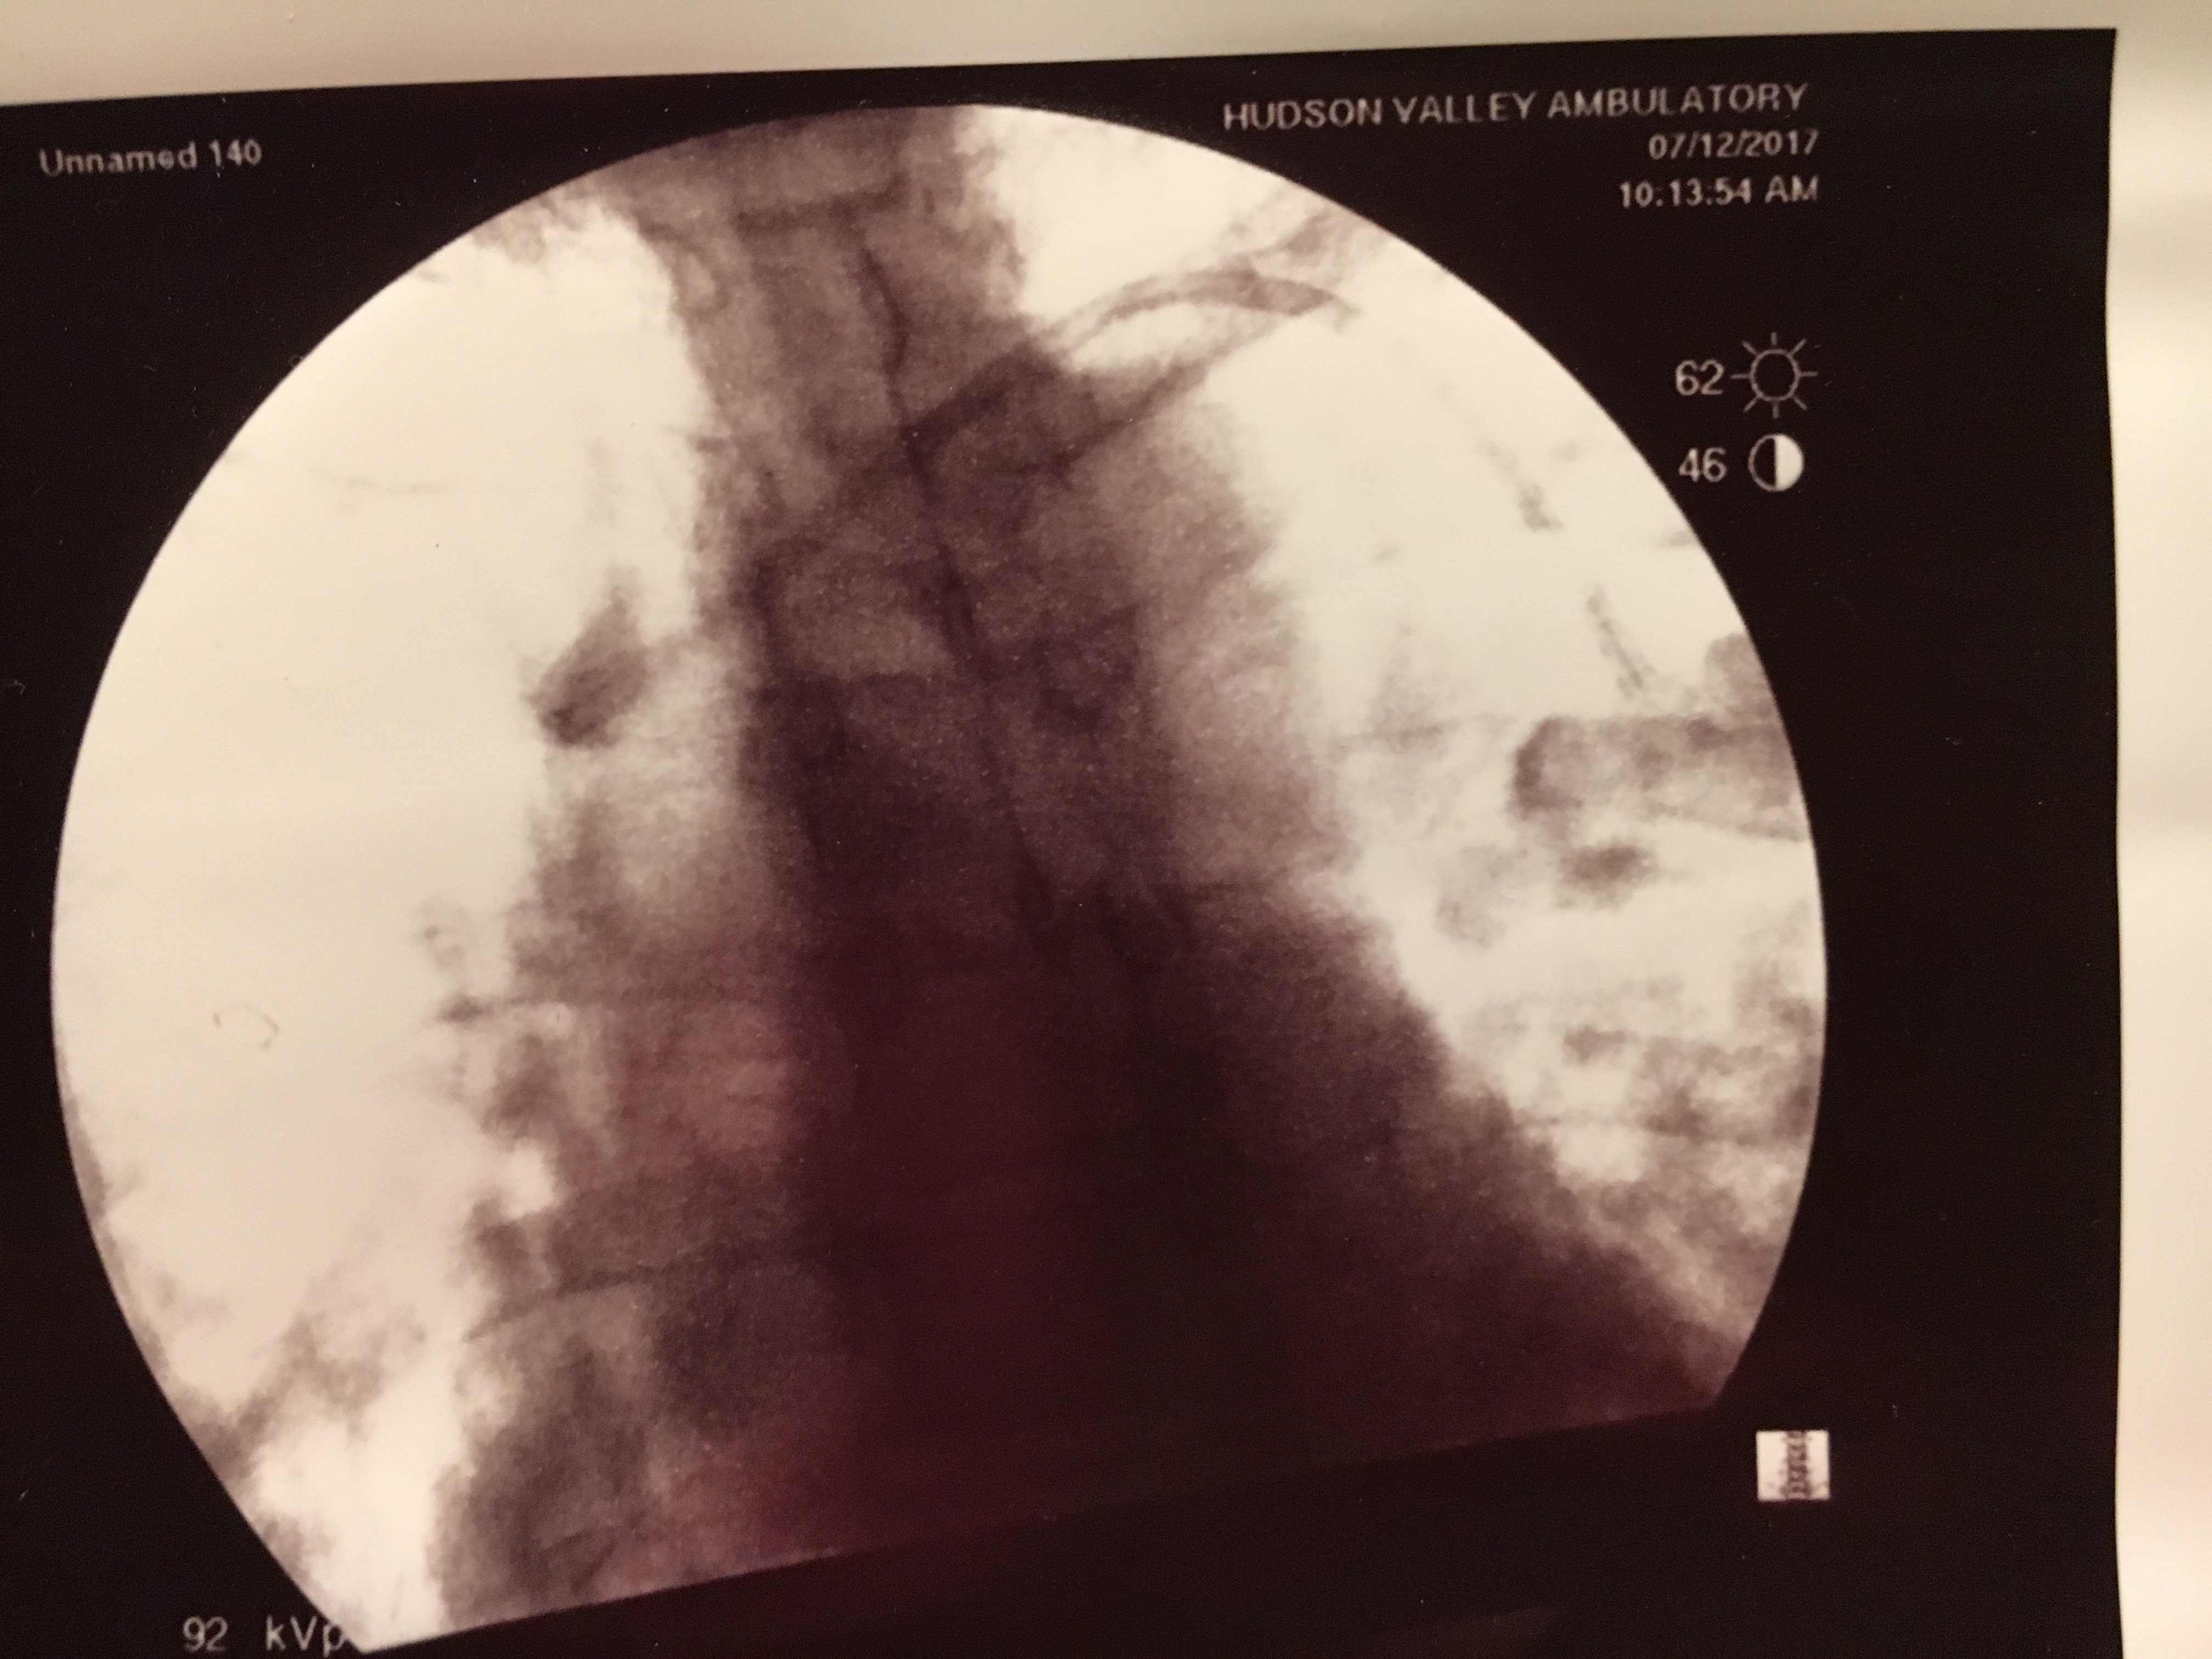

That same week, my son contracted a bad cold and cough. I tried to stay away from him but on St. Patrick’s Day, I woke up feeling like garbage. I had originally planned to march in the St. Patrick’s Day Parade in NYC with the LAOH. Nope. I stayed home and watched the parade on TV. The following day I was feeling worse. I went to Mass as I had been assigned to lector that day. I barely made it through the closing announcements I was so short of breath. I made an appointment to see my doctor on Monday the 19th. I hadn’t slept because I had been up coughing all night. The over the counter cough and cold medicine was doing nothing for me and my lungs sounded like the “Snap, Crackle, and Pop” of Rice Krispies in milk (or Pop Rocks in your mouth). My doctor put me on a Z Pack and low dose steroids. I told him that the WTC doctor told me that my breathing issues may not all be physical. He looked surprised and asked if the doctor actually knew my medical history! By Friday March 23rd, I was still feeling miserable. Any physical activity was draining. I was coughing a lot. After every cough attack, I would look at the Fitbit on my wrist and my heart rate would be hovering around 90. The Fitbit read “Fat Burn.” Who knew coughing was a work out? I went back to my doctor. He prescribed Levaquin and doubled the steroid dosage. On Palm Sunday, I was unable to go to Mass. Charles stopped and picked up Palms for me and my friend Patrick came and brought me Holy Communion. I stayed on my couch in my pajamas all day. Even getting dressed was a chore. In the evening, I took a hot bath hoping it would help. I got out of the tub and felt even worse. Charles wanted to take me to the Emergency Room. I used my nebulizer instead and once my heart rate slowed, I tried to fall asleep sitting up on the couch. I had been attempting to sleep sitting upright all week. As I was unable to sleep, I decided to color in my “Adult Coloring Book.” This became difficult because I kept getting cramps in my hands (and feet). On Monday the 26th, I was still feeling shitty and short of breath. I decided to use my nebulizer again. Whilst using my nebulizer, my hands and feet went numb and I got dizzy. I walked into my kitchen and leaned over my counter. When I went to stand up, I temporarily blacked out. My arms and legs just gave out and I saw black. Thankfully Charles was there to catch me. We called my doctor again. Back to his office. He took one look at me and sent me to the Emergency Room so that additional tests (Chest X-ray) could be done and so that I could get some IV steroids. (This time I is was in cubicle 9).

It was bizarre. My doctor called with some orders and the testing was done. An IV was started and a bunch of blood work was done, including tests to see if I had a blood infection (though these results would not be available for at least 48-72 hours). A nebulizer treatment was also done. The Chest X-Ray was negative (no pneumonia) as was the flu test. I did NOT have a fever. My temperature hovered around 97.8. The ER doctor didn’t think my wheezing sounded too bad and considered sending me home. I explained that my asthma issues didn’t always present with wheezing. It was worse for me when my chest was so tight there was no wheezing. He asked if I wanted to be admitted to the hospital! I’m not a doctor. What did my doctor say???!! The decision was ultimately made to admit me for a couple days so that I may receive high dose IV steroids. I was brought up to a room. More testing. A Chest CT. Also clear. I didn’t sleep at all Monday night. Breathing treatments every four hours and too many steroids pumping through my system.